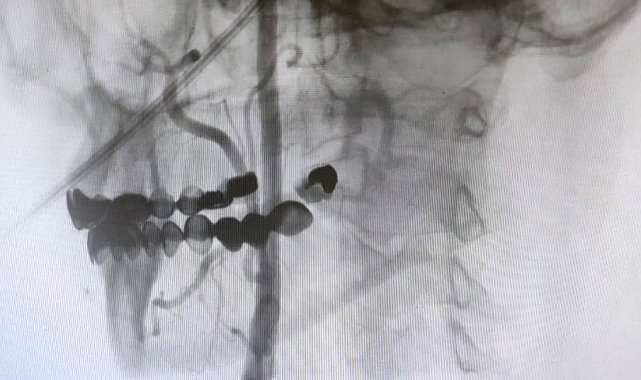

"Boyun damarlarını açma işlemi iki şekilde yapılabilir. Bir karotis endarterektomi dediğimiz ameliyatla bir diğer yöntem ise perkutan girişim dediğimiz stent yöntemiyle açılabilir. Biz kliniğimizde nöroloji ve kardiyoloji olarak bir konsey yapıyoruz. Damarı ciddi tıkalı olan ve buna bağlı felç geçirmiş hastalarda bu konseyde hastaya işlem yapıp yapmama kararı veriyoruz. Verdiğimiz karar çerçevesinde eğer hastaya işlem kararı vermişsek femoral arter dediğimiz kasık arterinden bir şitle 6 ya da 7 F çapında bir şitle ince bir boruyla bu damara giriş yapıyoruz ve boyun damarlarına ulaşıyoruz. Özellikle teller, filtreler ve stentlerle bu damarları açıp hastanın tedavisini gerçekleştiriyoruz. İşlem ameliyatsız olduğu için hastamız ertesi gün rahat bir şekilde problem olmazsa işlemde taburcu olabiliyor bu işlemden sonra. Bu işlemin yapılması için özellikle anjiografinin olduğu girişimsel nöroloji uzmanının ve girişimsel kardiyoloji uzmanının olduğu ve bu konuda yeterli vaka tecrübesine ve deneyime sahip uzmanların olduğu merkezler gerekir. Bunu yapabilmek için belli bir vaka sayısına ulaşmak ve bu konuda tecrübeli olmak gerekiyor. Biz de Manisa Şehir Hastanesi'ndeki girişimsel kardiyoloji ve nöroloji uzmanları olarak bu işlemi kliniğimizde efektif bir şekilde gerçekleştiriyoruz."